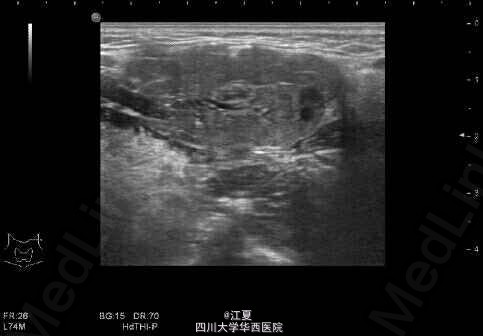

患者,女,19岁。发现颈部包块3月余。

包块无红肿,有轻微触痛。 超声示:左侧颌下腺长大,前后径约18mm,颌下腺导管增粗,最粗约5mm,内查见大小约4mm的强回声团伴声影。

诊断:左侧颌下腺导管结石伴扩张,左侧颌下腺长大。 治疗:摘除涎石(碎石机粉碎或手术)。症状较轻者可口服排石汤或其他辅助药物。预防应多饮水或进食酸性食品,促使唾液分泌,可使小涎石自行排出。